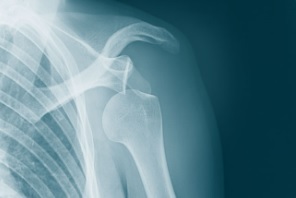

Симптомы вывиха плеча визуально заметны и не вызывают сомнений. В ряде случаев для подтверждения диагноза необходимо провести дополнительные диагностические методы, особенно, актуально для подвывихов. Рентгенография при вывихе показана абсолютно всем пострадавшим для подтверждения диагноза, определения нахождения суставных поверхностей костей и визуализации возможных костных отломков, чего в норме быть не должно. Клинически пациенты жалуются на боль, на полное отсутствие движений в плечевом суставе. Зачастую пострадавший обращается в травматологический пункт с такой рукой, примотанной на косынку. Самостоятельно снять ее он не может; приходится поддерживать второй здоровой рукой.